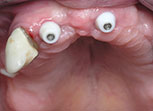

Dental implants is a highly predictable procedure for the replacement of missing teeth, restoring in a very effective way both function and aesthetics. Dentures ,when loose, can cause severe personal and social handicaps that can be overcome by using implant supported fixed restorations. Implants can also serve to replace one or several teeth and save healthy adjacent teeth from being used as support for fixed bridges. The procedure can be very simple or more complex depending on the severity of the case. Implants used nowadays are mostly made of medical grade titanium. They are placed in the jaw and connected to abutments to serve as support for crowns or bridges.

Implant supported crowns are so natural looking ! Cad Cam technologies and innovative restorative materials give to the crown a perfect esthetic result. You will forget that you ever lost a tooth. your confidence is regained and your self image is completely restored. you do not need to hide your smile anymore nor feel embarrassed because of ill-fitting dentures. you may have had difficulty chewing. You will regain your full function! Implant-supported crowns will look and feel just like your own!

Your treatment needs to be properly planed and the implants and crowns placed under the best conditions to ensure long term success. With diligent maintenance, implants can last a lifetime. Long-term studies show very high success rates.

Because a dental implant will replace your tooth root, the bone is preserved. With a bridge, some of the bone that previously surrounded the tooth resorbs in time , part of a natural remodeling process Dental implants integrate with your jawbone, helping to keep the bone healthy and intact.

A single implant can be more esthetic and easier to keep clean than a bridge. Also, after several years of function, gums can recede around a bridge causing unesthetic exposure of the bridge margins. Resorbed bone beneath the bridge can be the cause of an unattractive smile. Also, the cement holding the bridge in place can wash out, allowing bacteria to proliferate unreached by the tooth brush resulting in decay of the anchoring teeth and bridge loss

Immediate Loading

Immediate loading refers to attaching a crown or a bridge to a newly inserted implant(s) at the time of implant placement. Simply put, the various procedures that were traditionally spread out over 4-6 months are carried out simultaneously. This means that you will always have fixed teeth during the treatment. Sometimes it is even possible to insert the final bridge at the time of implant placement.

Immediate loading is not always possible but may be indicated when selected factors are present: bone quality and quantity, primary stability when placed in bone, implants number and location and loading conditions .Having vast experience placing and immediately restoring implants will further enhance outcome. Our periodontists at the Beirut Dental Specialists clinic use the immediate loading technique with excellent success rates and consistantly great clinical results

The All-on-4 treatment concept was developed to provide edentulous patients with a functionally effective restoration using only four implants for an immediately loaded full-arch prosthesis. The four implants support a fixed prosthesis with 12 to 14 teeth and it is placed immediately on the day of surgery.